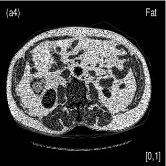

III.4 Pelvis Data Study

We also evaluated the proposed PWLS-TNV- method using clinical pelvis data. The patient’s pelvis data was acquired by Siemens SOMATOM Definition flash CT scanner using DECT imaging protocol. Table 4 lists acquisition parameters in the pelvis data scan. Fig. 5 shows the high- and low-energy CT images of the pelvis data. Fig.5 (b) shows selected basis materials, bone, iodine, muscle, fat and air, and their assosicated ROIs highlightened in white dashed line circles. We implemented the Direct Inversion method in mendonca2014a and used its results as the initialization for the PWLS-EP-LOOP xue2017statistical and the proposed PWLS-TNV- method. Fig. 6 shows the decomposed material images by the Direct Inversion, the PWLS-EP-LOOP and the PWLS-TNV- method. Table 5 summarizes the means and noise STDs of the decomposed material images by the above three methods. The volume fraction (VF) accuracies are , , and for the Direct Inversion method, the PWLS-EP-LOOP method and the proposed PWLS-TNV-, respectively. Compared with the Direct Inversion and PWLS-EP-LOOP method, the proposed method improves the VF accuracy by and respectively. The proposed PWLS-TNV- method decomposes basis material images more accurately, suppresses noise and decreases crosstalk, while retaining spatial resolution of the decomposed images compared to the other two methods.